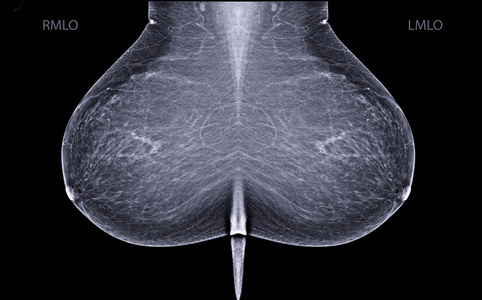

乳腺钼靶和超声对照

图片尺寸893x390

注意| 乳腺x线摄影报告规范化用语中,请不要再用"钼靶"一词

图片尺寸1080x813